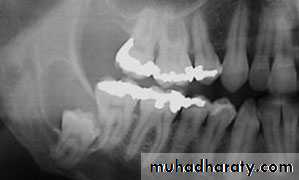

Odontogenic cysts ( dental cysts):1-periodontal cysts:is formed from epithelial rests or remnants in the periodontal membrane. These cysts are all of inflammatory origin. The usual location is along the lateral surface of the teeth. Which termed lateral cyst or at the apex of Cysts of inflammatory nature in edentulous area are termed residual. These result from incomplete surgical removal of pathological tissue at the time an infected tooth is extracted. These cysts are commonly lined by stratified squamous epithelium.

Round cell inflammation and other signs of chronic inflammation are usually found. The small periodontal cyst can often be enucleated through the alveolar socket after removal of the involved tooth. It is frequently much better to elevate a surgical flap and remove the cyst by the labial or buccal approach. Large periodontal cyst treated either by enucleation or marsupialization tooth roots that protrude into a bone cavity after enucleation of a cyst should be amputated after proper root canal therapy.